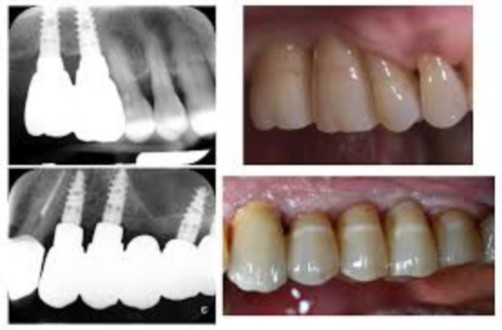

Are medical devices surgically implanted into the jaw to restore a person’s ability to chew or their appearance. They provide support for artificial (fake) teeth, such as crowns, bridges, or dentures.

Replacing a lost tooth with a dental implant can significantly improve the patient’s quality of life and health.

The dental implant body is surgically inserted in the jawbone in place of the tooth’s.

An implant-supported denture is an oral appliance that replaces several teeth at once.

It’s similar to a traditional denture. But instead of resting on top of your gums, an implant-supported denture attaches directly to your jawbone using dental implants.

Fixed implant-supported dentures

A fixed denture — sometimes called a hybrid denture — attaches permanently to dental implants in your jawbone. You can’t remove it at home, but your dentist can remove it for maintenance when necessary.